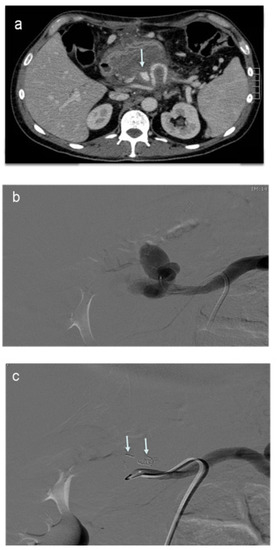

4. Transcatheter Embolization (Stent–Graft)